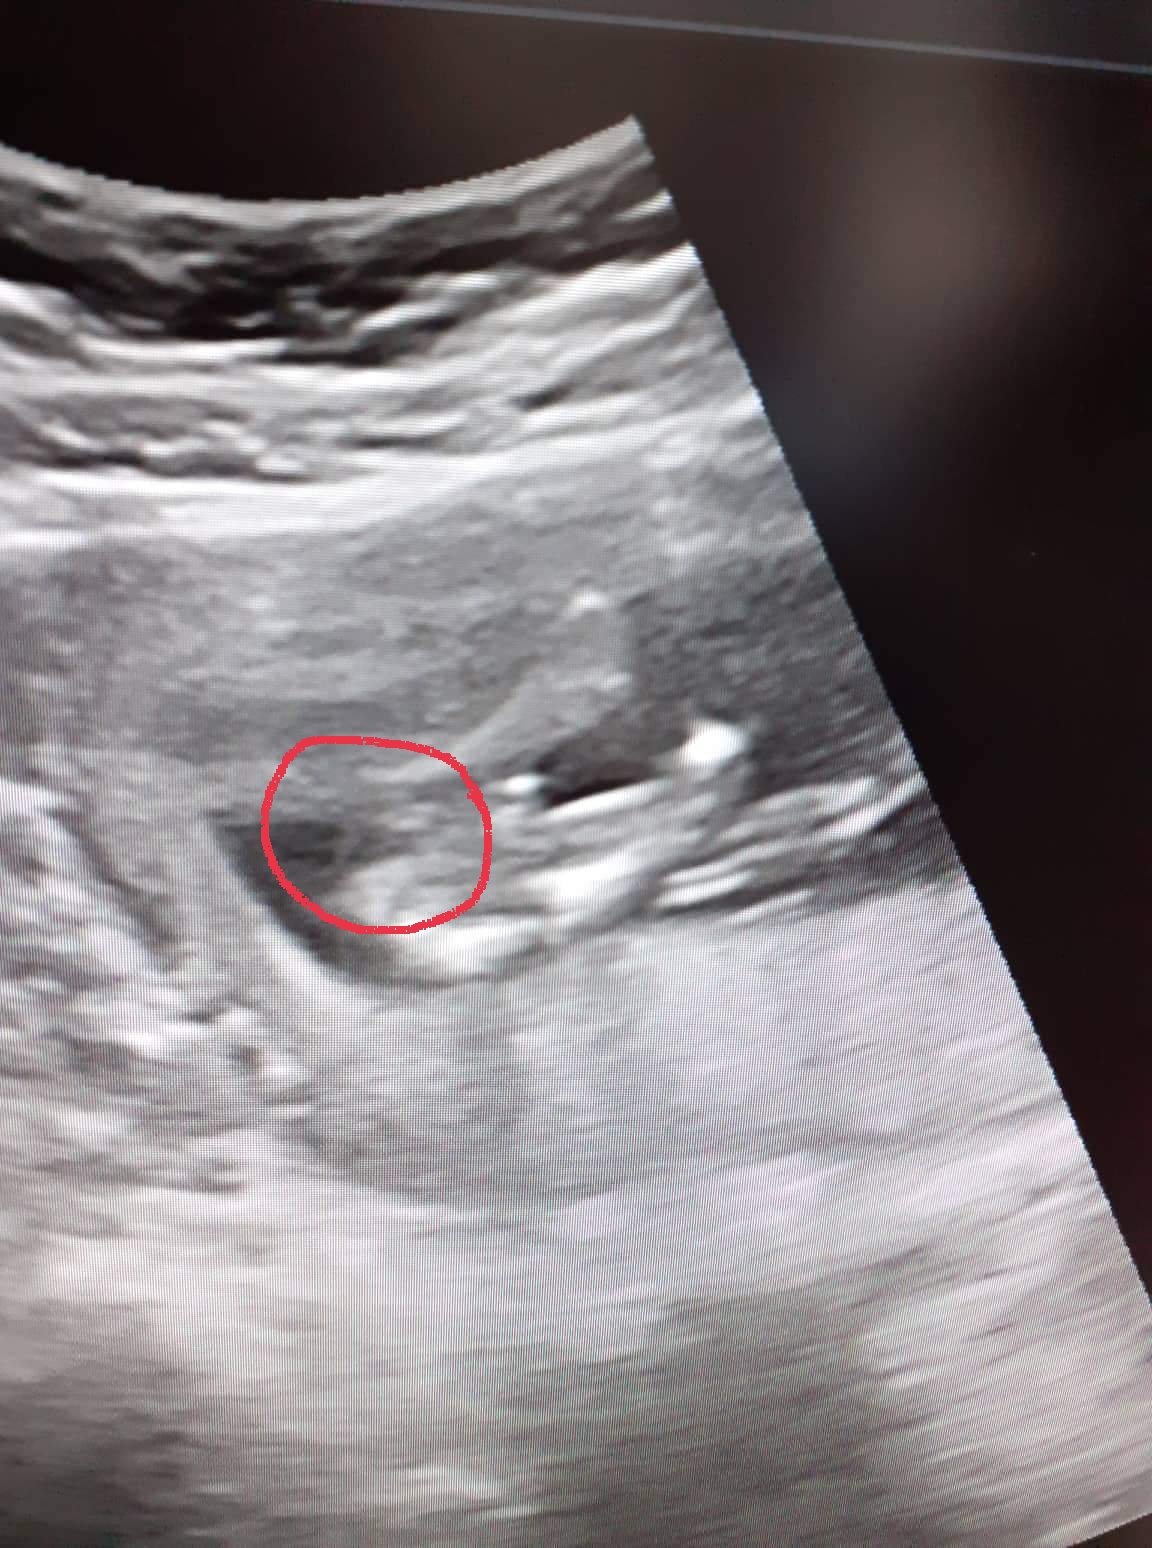

Řekla bych holka, ale ta kvalita je nic moc :D Proč ses nezeptala u doktora? 🙂